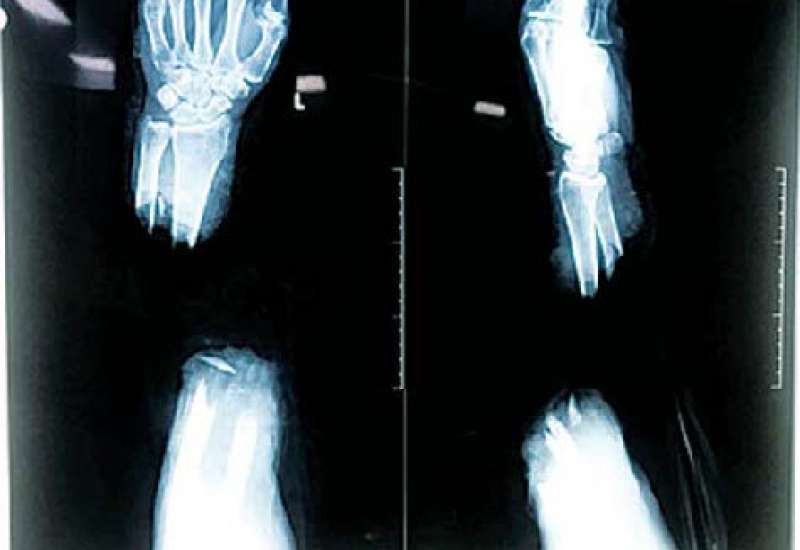

ရန်ကုန်ပြည်သူ့ဆေးရုံကြီး၌ ဧပြီ ၁၄ ရက်တွင် လက်ကောက်ဝတ်အထက်မှ ပြတ်တောက်သွား သောလက်အား ပြန်လည်ဆက်ပေးသည့် ခွဲစိတ်ကုသမှုကို အောင်မြင်စွာ ဆောင်ရွက်ပေးနိုင်ခဲ့ကြောင်း သိရသည်။